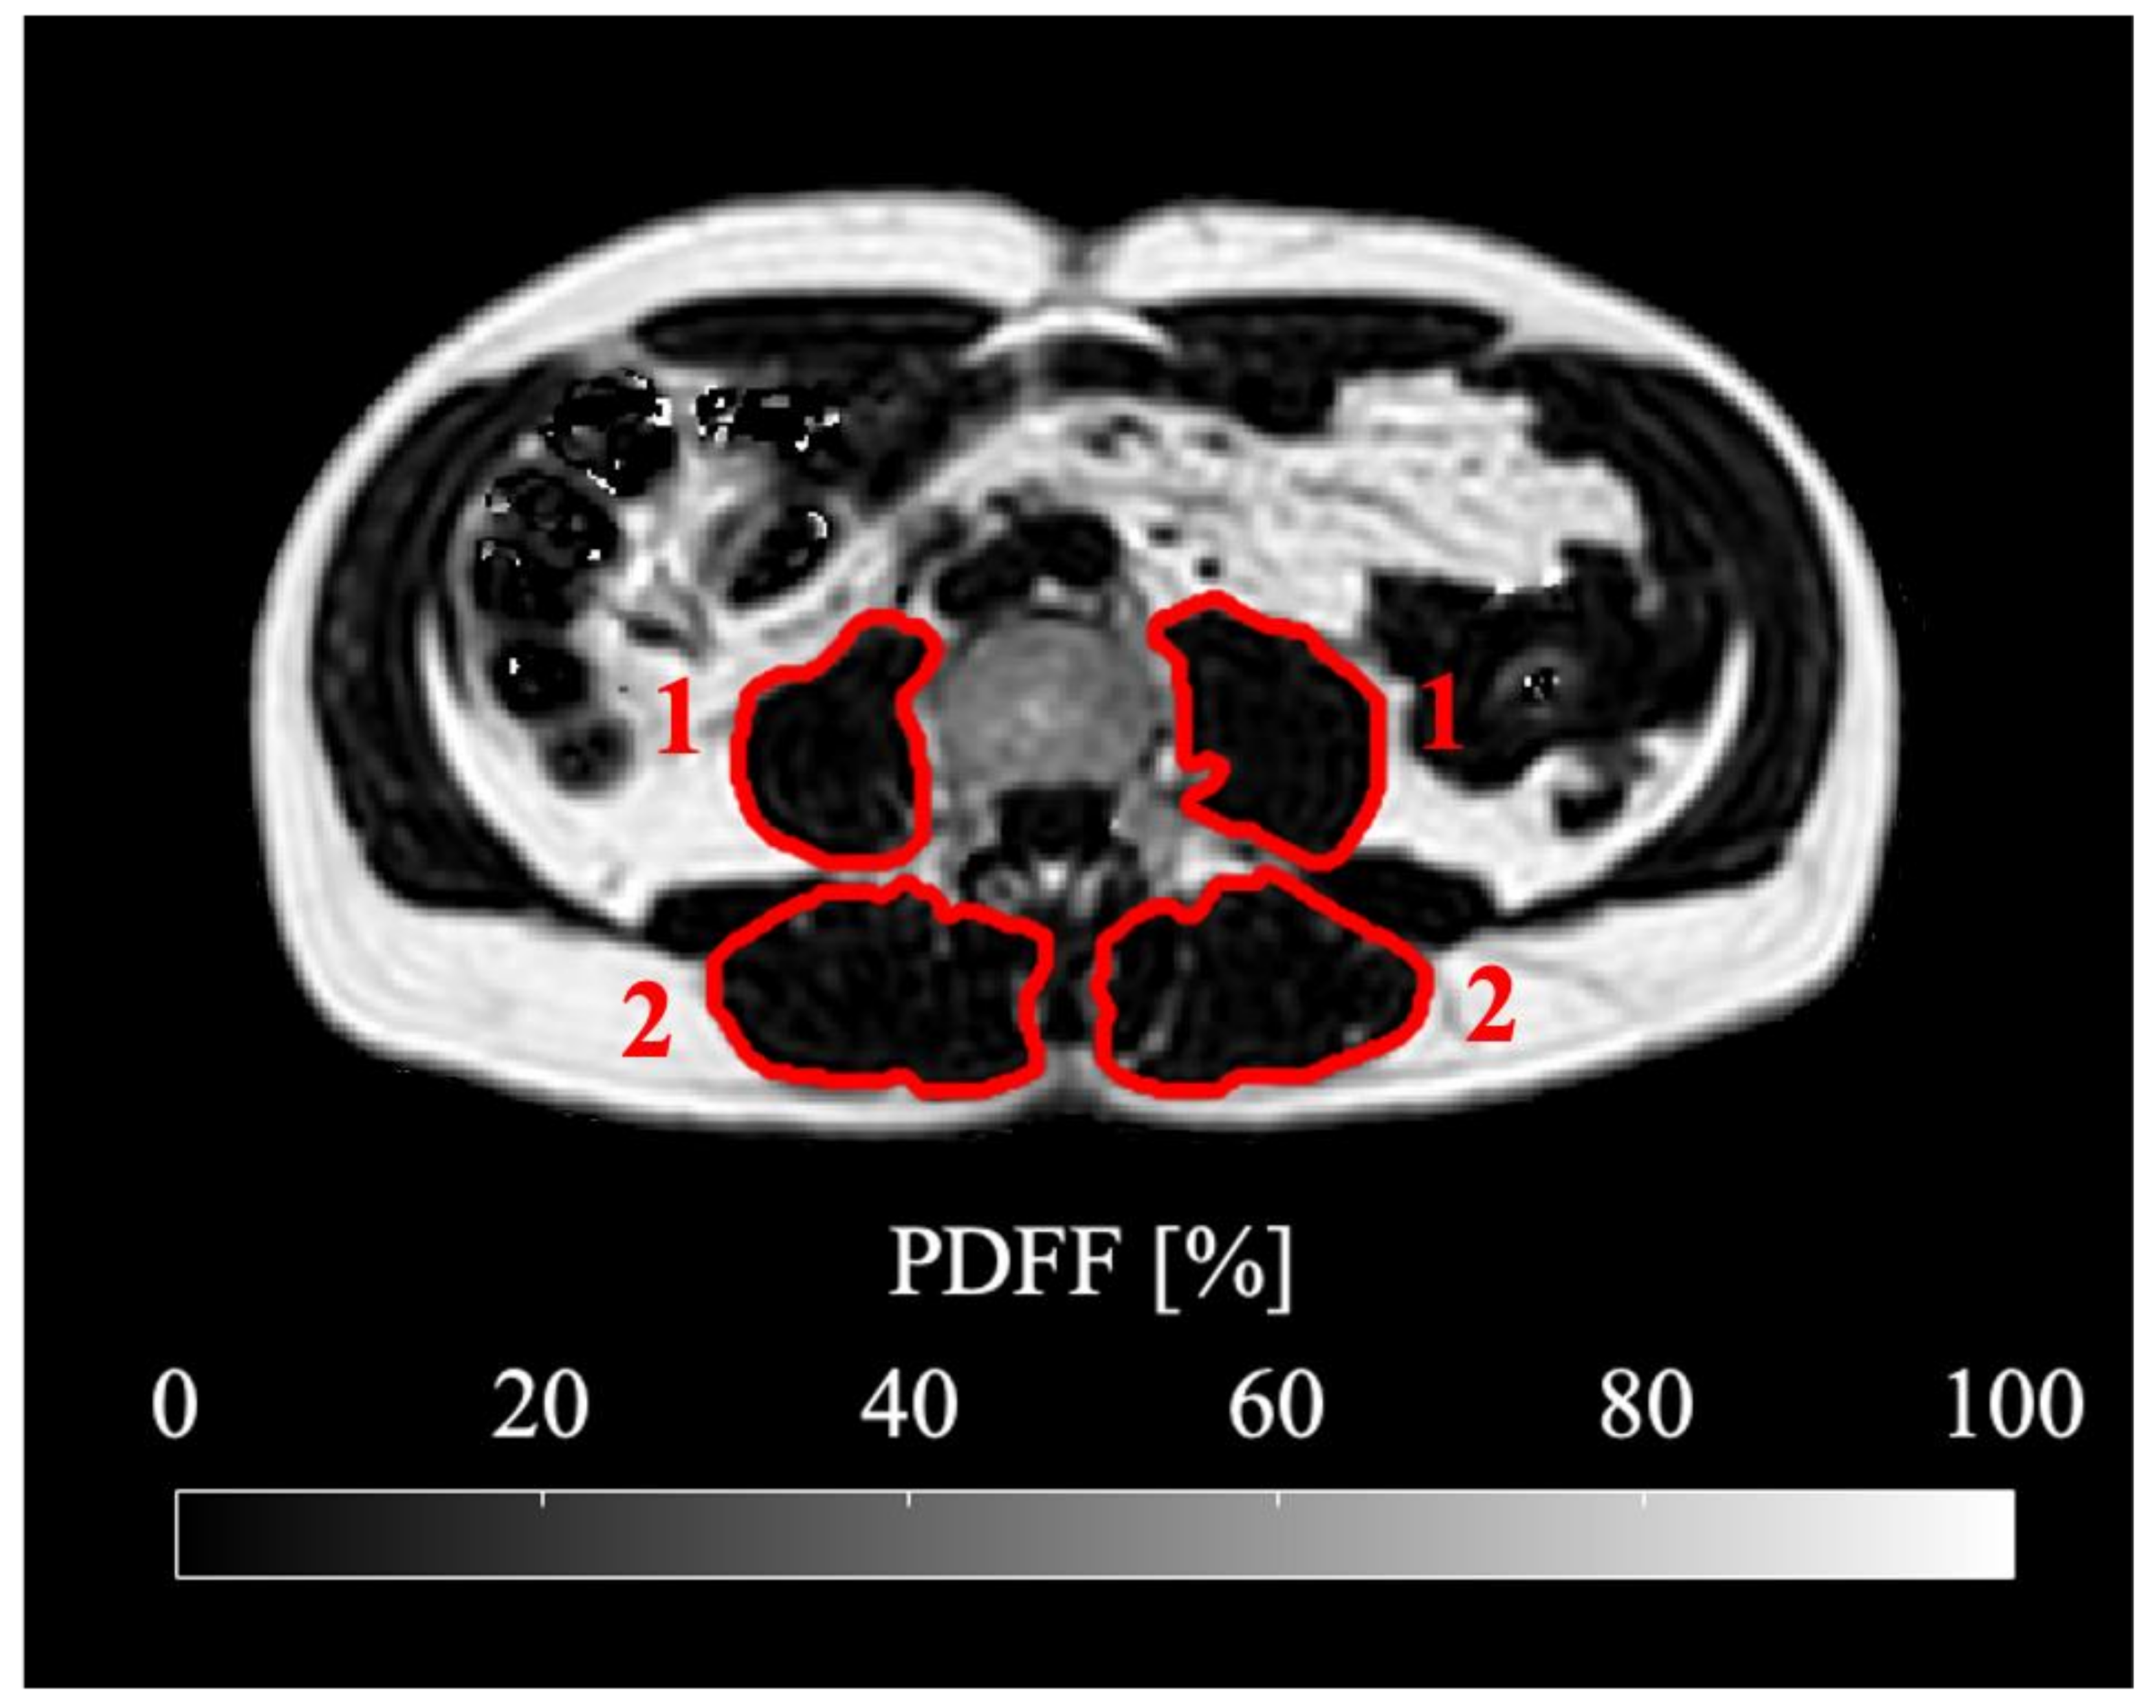

Figure 1.

Representative segmentation of psoas (1) and erector spinae (2) muscle shown in the PDFF map at the level of the fourth lumbar vertebra (L4). The subject is a 60-year-old male with a BMI of 26.0 kg/m2 suffering from ductal adenocarcinoma of the pancreas.